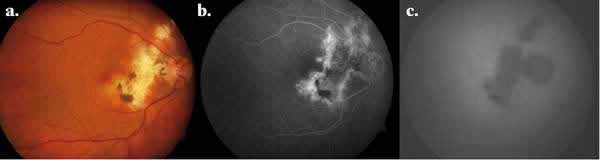

– Angiografía con fluoresceína (AFG): Los hallazgos no son patognomónicos. Las áreas atróficas se visualizan hipofluorescentes en tiempos precoces por la atrofia coriocapilar, con hiperfluorescencia progresiva de los bordes y eventual tinción escleral (fig. 3). Las lesiones activas bloquean precozmente la fluoresceína y muestran una tinción difusa con fuga progresiva en tiempos tardíos (fig. 4). En las fases de actividad, con frecuencia permite identificar tramos de vasculitis perilesionales (fig. 5) (2).

Fig. 4: Aspecto (a) oftalmoscópico y (b) angiográfico de paciente con lesión

activa (flecha) y lesión inactiva (punta flecha).

Fig. 5: Aspecto (a) oftalmoscópico y (b) angiográfico de paciente con CS activa

y vasculitis (flecha).